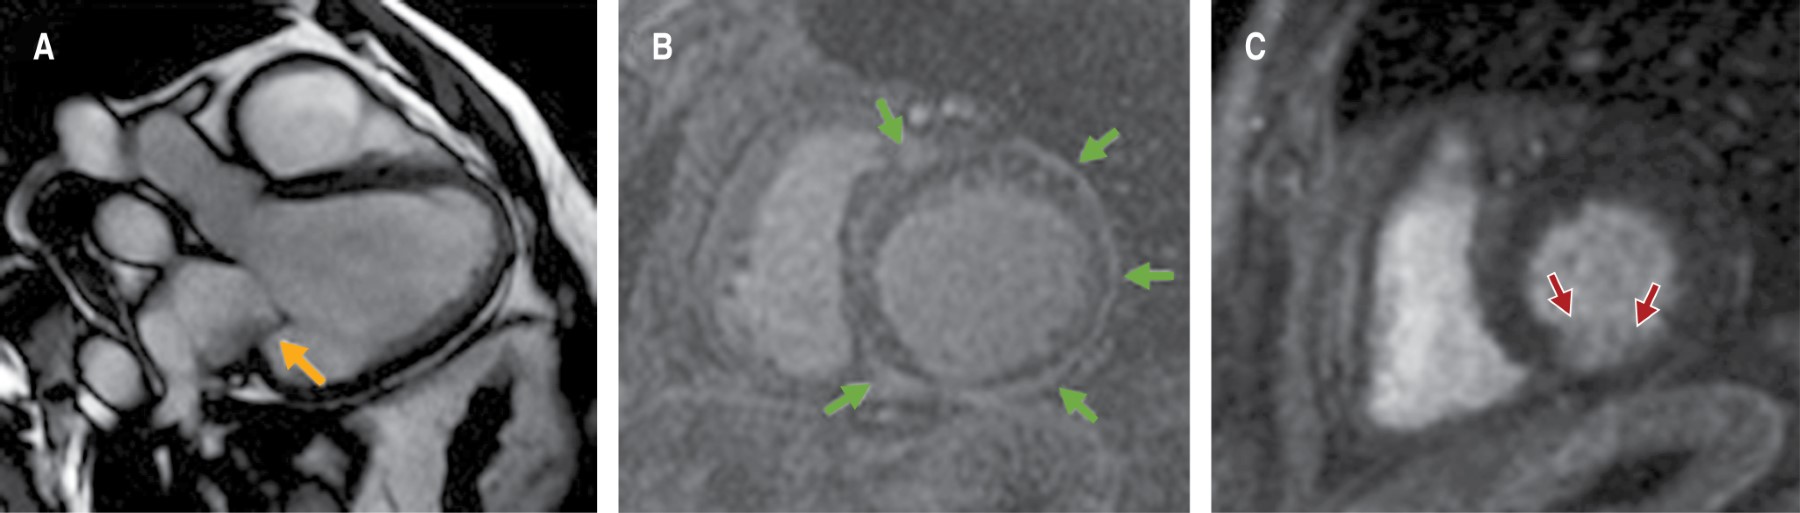

Figura 2